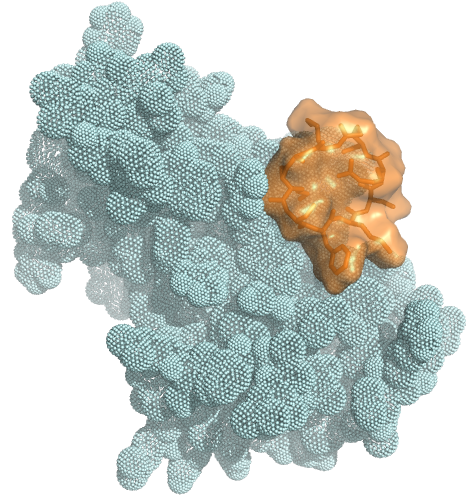

Our Trilomer® platform of mirror-image cyclic peptides enables the targeted delivery of potent chemotherapy drugs for the treatment of cancer.

Trilomer® mirror-image drug-conjugates overcome the liabilities of ADCs and peptide-drug conjugates by using 100% D-amino acids, which inherently possess high resistance to proteases (preventing premature release of chemotherapy drug) and also exhibit low uptake by renal scavenger receptors (reducing toxicity to healthy tissues and organs).

Trilomer® drug-conjugates rapidly penetrate tumors and bind specifically to cell-surface proteins on cancer cells, after which they are rapidly internalized, releasing the chemotherapy drug directly inside the cancer cell.

"Fast In / Fast Out" mechanism

increases tumor uptake and reduces toxicity

Peptides made from 100% D-amino acids

are poor substrates for renal scavenger receptors

Large binding surface allows targeting

to any cell-surface protein